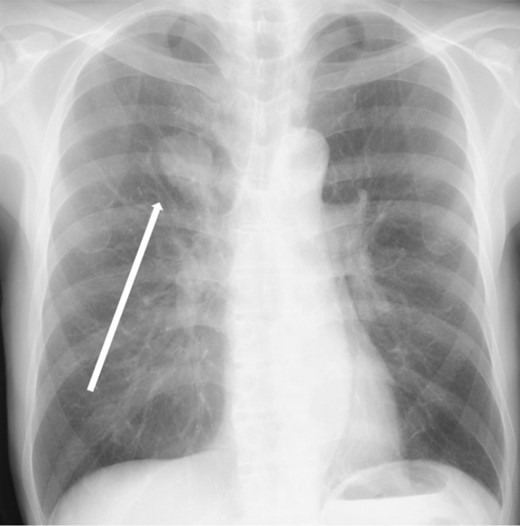

The patient was a 73-year-old man. He had a history of arteriosclerosis obliterans in the lower extremities, transient atrial fibrillation, and was consuming two antiplatelet agents. The patient had a fever within the range of 38°C. Blood tests showed an elevated white blood cell (WBC) count of 31.6 × 103/μl (neutrophil, 90.2%), CRP of 9.67 mg/dl, and APTT of 125.4 s. Chest radiography revealed an abnormal shadow in the upper lobe of the right lung (Fig. 1). Contrast-enhanced chest CT revealed an irregularly shaped mass, 43 × 33 × 28 mm in size, in the upper lobe of the right lung (Fig. 2). 18F-fluorodeoxyglucose-positron emission tomography showed abnormal accumulation with a maximum standardized uptake value of 28.4 in a pointed lesion in the upper lobe of the right lung (Fig. 3). A bronchoscopic biopsy was performed, and the patient was diagnosed with non-small cell carcinoma.

Chest computed tomography (CT) findings. An irregular mass 43 × 33 × 28 mm in size was found in the upper lobe of the right lung, which was suspected to be primary lung cancer.